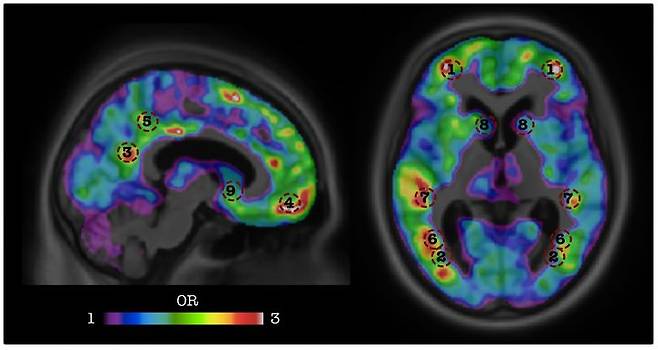

36. 치매 예측

캐나다 맥길대학 정신건강연구소 산하 ‘중개신경영상랩’ 연구팀은 치매 예측에 인공지능 기술을 사용했다. 연구팀은 ‘알츠하이머병 신경영상 이니셔티브(ADNI)’가 가지고 있는 ‘경도인지장애(MCI)’ 환자의 PET(양전자방출단층촬영) 자료를 인공지능에 학습시켰다. 이 과정으로 치매가 발생하기 약 2년 전에 치매를 예측할 수 있는 알고리즘을 만들었는데 그 정확도는 84%에 이른다. 나아가 이 연구 결과는 치매 환자를 조기 관리하고 치료 연구를 가속할 수 있는 바탕을 마련할 것으로 기대받고 있다.